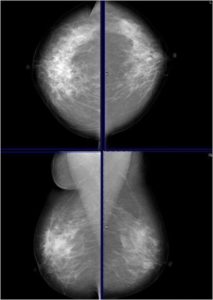

Bilateral Mammograms revealed increased reticular densities in the upper half of the right breast. A 16 mm well defined nodule seen in the left subareolar region. BIRADS 3/4 Bilateral breast ultrasound revealed extensively dilated ducts showing thickened walls and intra ductal contents corresponding to the increased reticular densities on the mammogram of right breast. Left breast revealed a 17 x 10 mm well defined low echogenic lesion with posterior enhancement in the left subareolar region. BIRADS 3 MRI showed segmental clumped / clustered ring enhancement extending from 10 to 2 O’ clock position in the right breast with extensive ductal branching and intraluminal contents extending till the nipple suspicious for DCIS. Left breast revealed a benign 16 x 14mm well defined nodule in the lower inner quadrant close to the nipple. BI-RADS-4.